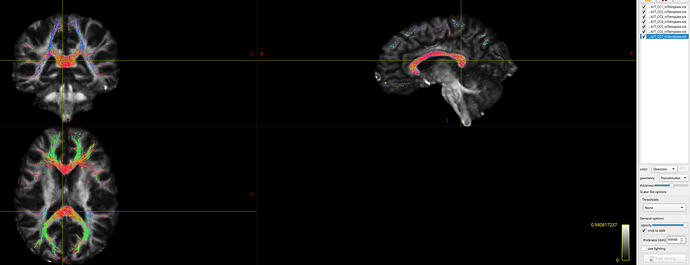

I have resolved the issue of transforming .tck files from individual space to template (ORG) space. My solution is as follows:

(1) First, we performed skull stripping on the T1w2dwispace.nii.gz image to obtain T1w2dwispace_brain.nii.gz.

(2) The skull-stripped image (T1w2dwispace_brain.nii.gz) was then registered to the T1_ORG_template.nii.gz using ANTs, yielding the transformation files (T1w2dwi_toTemplate_0GenericAffine.mat and T1w2dwi_toTemplate_1Warp.nii.gz).

(3) The resulting transformations were subsequently applied to the .tck files using tcktransform. However, due to differences between ANTs and MRtrix3 in how spatial transformations are represented and applied, additional conversion steps are required to ensure compatibility. A sample implementation is provided below for reference:

tcktransform "${TCK_IN}" mrtrix_tck_deformation.mif T_CC1_inTemplate.tck